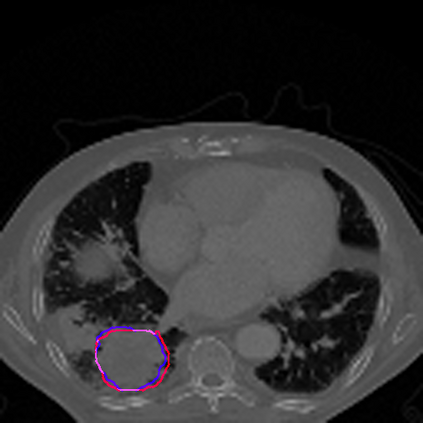

Lung cancer is a leading cause of death in most countries of the world. Since prompt diagnosis of tumors can allow oncologists to discern their nature, type and the mode of treatment, tumor detection and segmentation from CT Scan images is a crucial field of study worldwide. This paper approaches lung tumor segmentation by applying two-dimensional discrete wavelet transform (DWT) on the LOTUS dataset for more meticulous texture analysis whilst integrating information from neighboring CT slices before feeding them to a Deeply Supervised MultiResUNet model. Variations in learning rates, decay and optimization algorithms while training the network have led to different dice co-efficients, the detailed statistics of which have been included in this paper. We also discuss the challenges in this dataset and how we opted to overcome them. In essence, this study aims to maximize the success rate of predicting tumor regions from two dimensional CT Scan slices by experimenting with a number of adequate networks, resulting in a dice co-efficient of 0.8472.